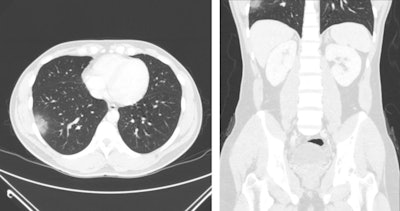

All year, CT helped illuminate more surprising manifestations of COVID-19 and track its transmission. A team from the University of Maryland School of Medicine in Baltimore found that nonchest CT exams performed at the behest of emergency department physicians often also captured pulmonary findings suspicious for COVID-19. In addition, Temple University Health System researchers shared a case of a woman who was diagnosed with the illness when she underwent CT staging for breast cancer.

CT has much to offer for long-term tracking of COVID-19 patients, according to Dr. Seth Kligerman, chief of cardiothoracic imaging at the University of California, San Diego.

"CT is helpful in assessing complications from COVID-19, such as pulmonary thromboembolism," he told AuntMinnie.com. "We are also starting to perform follow-up imaging in patients who had severe lung injury due to [COVID-19] and show variable degrees of lung healing. While the lungs in some patients do appear to nearly completely recover, at least on a macroscopic level, others will wind up with permanent fibrosis, which may lead to debilitation."